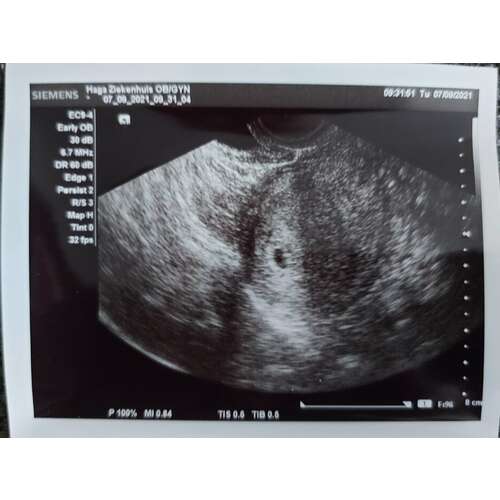

Hier goed! Gister een echo gehad ivm medisch traject. Maar overdragen aan de vk want het zit in elk geval in mn baarmoeder🥳 Verder hier goed, alleen erg moe en misselijkheid begint te komen helaas... ga je een bloedtest laten doen?

Wat goed nieuws!! 🤩 maar ik weet nog niet zo goed wat ik op zo’n echo moet herkennen😅 is dat een vruchtzakje?

Oh en idd een vruchtzakje met een dooier😅